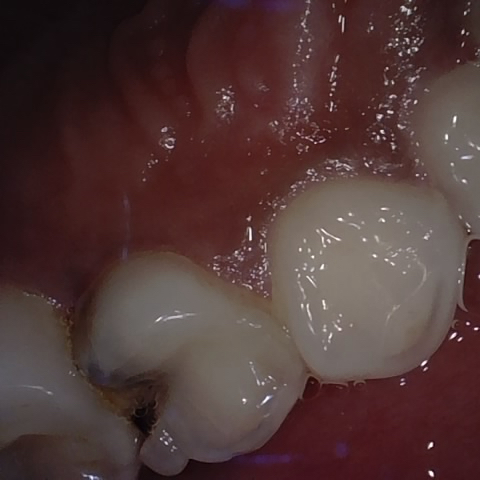

Annotated as "Good"